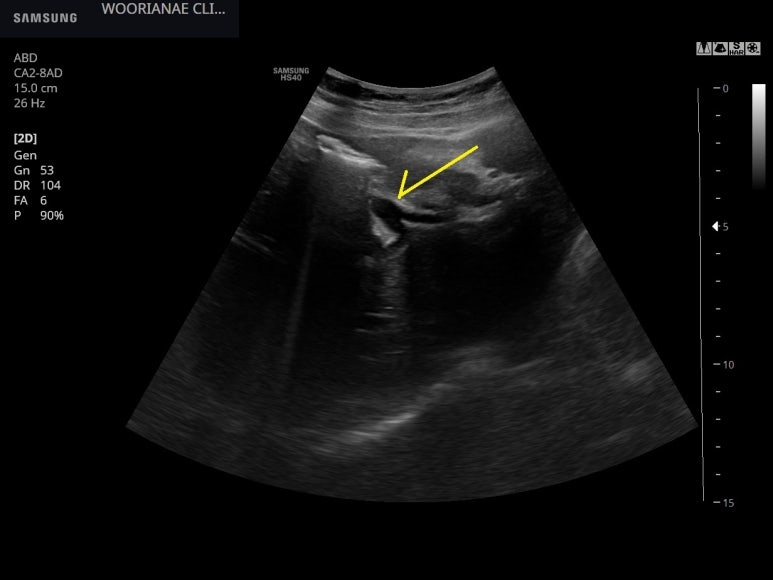

늑간뷰에서 총담관이 14.5 mm 가지 확장된 모습

우측의 담도가 담도 분지부를 지나서도 꽤나 확장되어 있다. 좌측에서는 관찰되지 않음.

총담관 퍠색도 정도의 차이

간내 담도의 확장은 없는

총담관 확장의 재확인